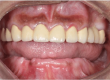

Systemic lupus erythematosus (SLE) presents as a chronic inflammatory autoimmune disease that can often demonstrate multisystem involvement. Since, immune-suppressive drugs are used in the treatment of this disease, it can possess an elevated risk of infection and delay healing. Moreover, damage to the salivary glands in this disease leads to reduced salivation. Together, these complications can be a primary concern in dental treatment procedures owing to inability to maintain oral hygiene and risk of implant failure. This is the first case report in literature to our knowledge and it represents a treatment option and procedure for immediate full mouth rehabilitation after extraction without raising flaps using basal cortical screw implant in a patient who was on corticosteroid for over 20 years as she was diagnosed with Systemic Lupus Erythematosus. Since there are very few cases of SLE reported in literature with the use of oral implants, treating these patients can often pose a challenge.